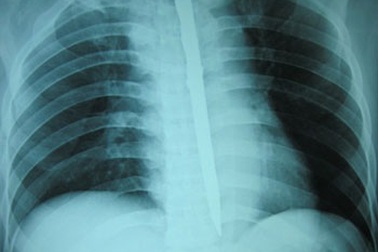

Nuốt dao nhọn dài 15cm để… tự tửVì muốn tự tử, anh Lê Hữu H. (37 tuổi, Thanh Hoá) đã nuốt con dao dài 15cm. Con dao nhọn này đã chui tọt qua cuống họng, chọc thủng thực quản và nằm dọc trong lồng ngực, may mắn không gây nguy hại tính mạng người bệnh.